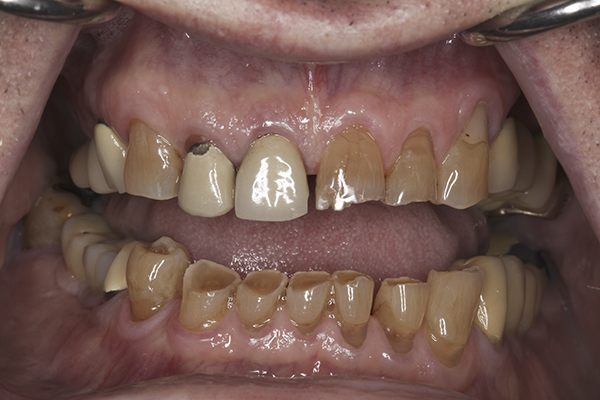

(10.) Preoperative anterior, closed view. Note the end-to-end occlusion of the anterior teeth and the wear on the incisors and centrals resulting in no anterior or canine guidance.

Figure 10

(7.) Preoperative anterior, open view. Note the significant amount of wear, erosion, and abfraction lesions.

Figure 7